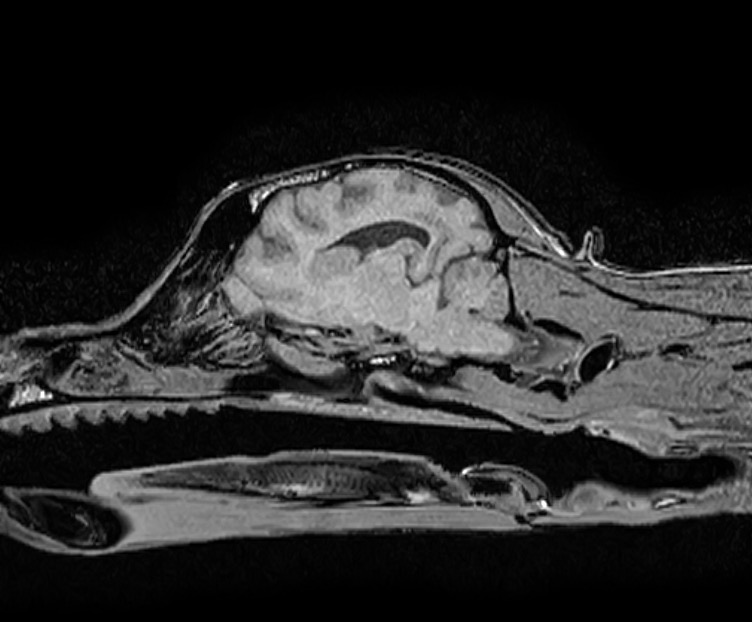

頭部MRI検査では重度の脳圧亢進所見(脳の浮腫)、大脳の後頭葉領域に炎症所見が認められ、脳炎(特に肉芽腫性髄膜脳脊髄炎:GME)が第一に疑われるという結果でしたが、

脳圧亢進所見が重度のため脳脊髄液(CSF)検査が実施できず、確定診断には至りませんでした。

しかし、やはり第一に肉芽腫性脳脊髄炎(GME)の可能性が高いことより、ステロイドや抗痙攣薬による治療を開始し、2週間後に再度頭部MRI検査を実施し、経過を評価することとなりました。